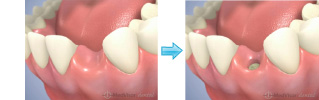

インプラント治療とは、歯の無くなった部分に人工の歯根を顎の骨に埋め込み、その上に人工の歯を被せて、自分の歯のように「しっかり噛める」ようにする治療です。

入れ歯は、バネを引っかけた歯に負担がかかり、ブリッジは、健全な歯を削らなくてはいけない場合があります。インプラントは、それ自体独立して、歯槽骨に埋め込まれて固定させるため、他の歯に負担がかかりませんし、むしろ、他の歯への負担を軽減させられ、健全な歯を削ずることも避けられます。